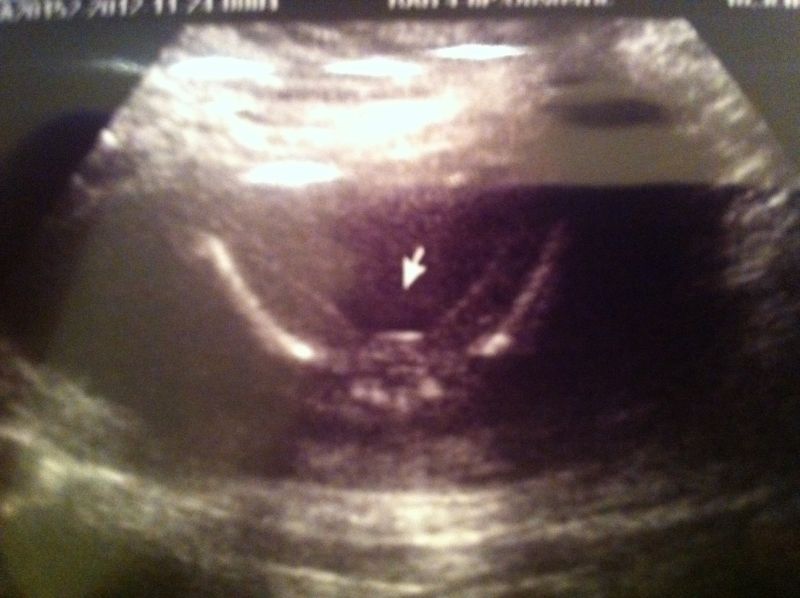

After a total melt down, I decided to pay for a private ultrasound: According to their website they can tell as early as 16 weeks: I had this sonogram at 16 weeks 4 days. I explained the situation and requested that most senior sonographer do the scan, we had a woman with over 10 years experience: she tells me she is 100% sure that we are having a girl. She pointed out that absolutely nothing is sticking out between the legs and assured me that we got a great "Potty Shot". I see what shes talking about, but I also don't see the "3 lines" that everyone talks about that definetly signifes girl.

Can you please put my fears to rest and let me know what you think? I'm seriously considering having another scan the morning of the party when I'll be 17 weeks 4 days but the sonographer assured me that it would likely be a waste of money because she would come to the same conclusion.